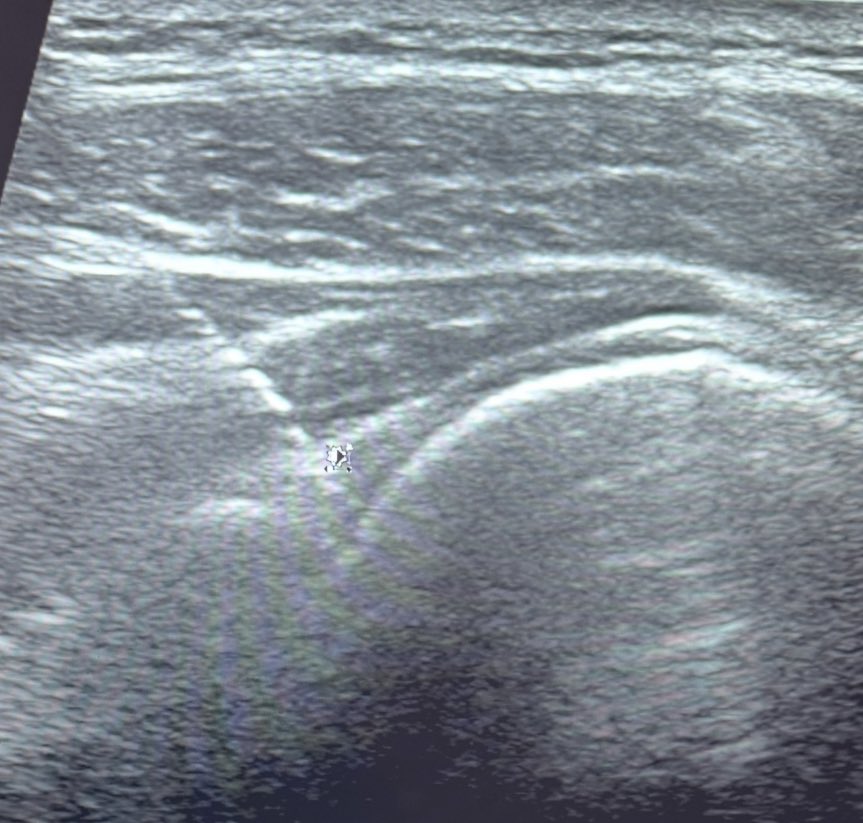

الاصبع الزنادي " trigger finger " حاله مرضيه تجعل الاصبع عالقاً في حالة الثني ( ثني الاصبع ) مما يصعب الحركه بسبب ضيق حول غمد الوتر في مناطق معينه من اصبع اليد. قد يصعّب وجودها الحركات اليوميه الاعتيادية باليد كالاكل والكتابه مثلاً وغيرها.. غير مقلقه في اغلب الحالات ويمكن